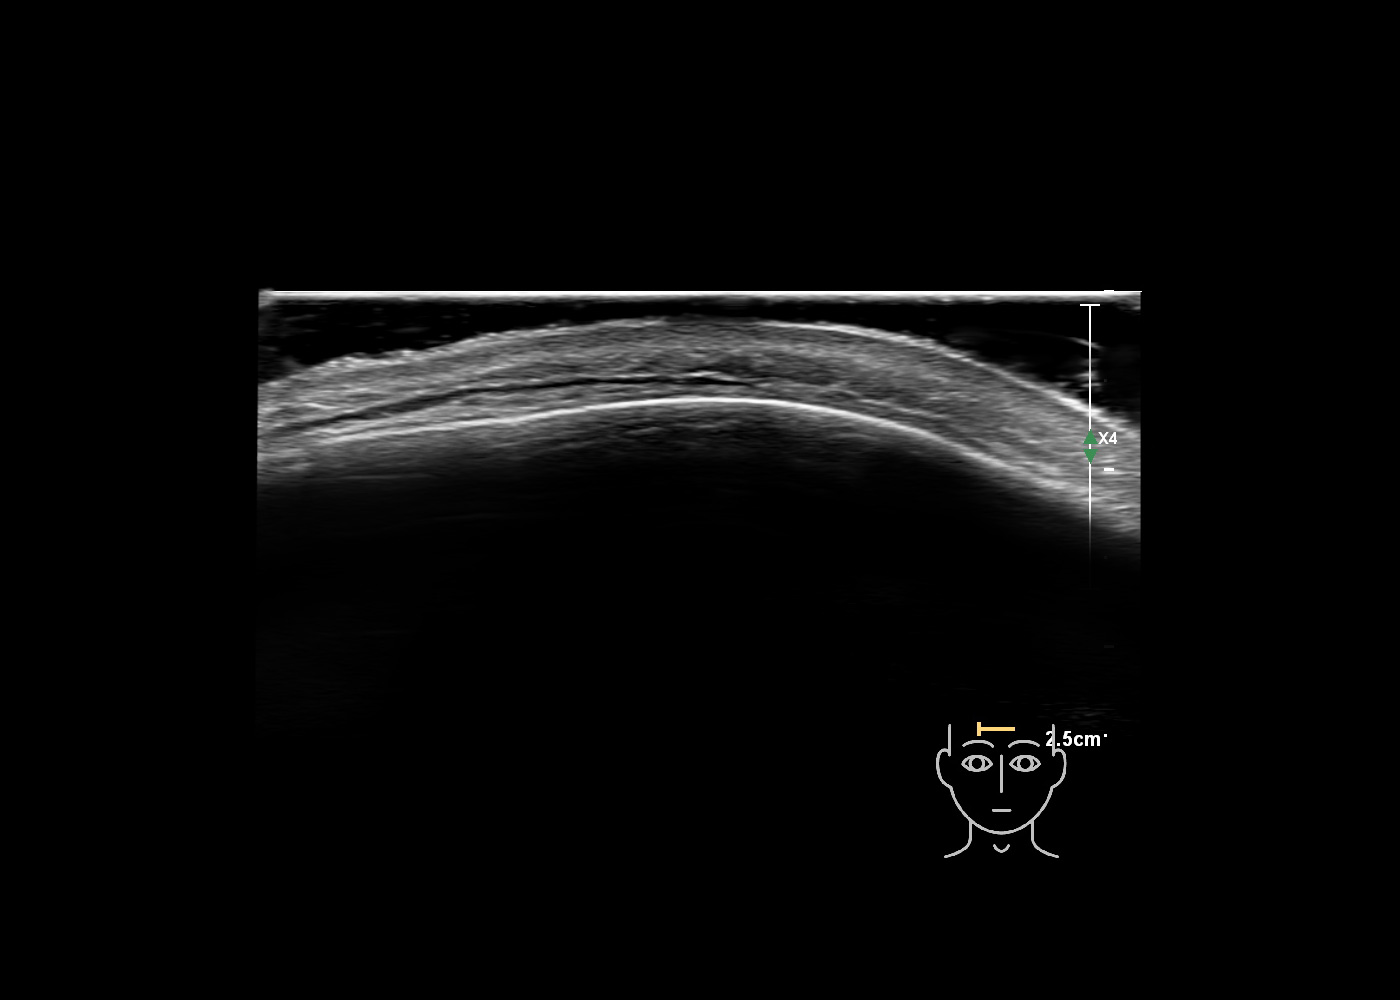

In this section you will learn more about the different layers of the face with the use of ultrasound. When you click on the secondary ultrasound image, you will see the different structures as an overlay. This will help to train yourself to recognize the different layers of the face.

Study the first image to recognize the different layers. If you are sure about the layers, swipe to the second image to view the answer (if applicable).